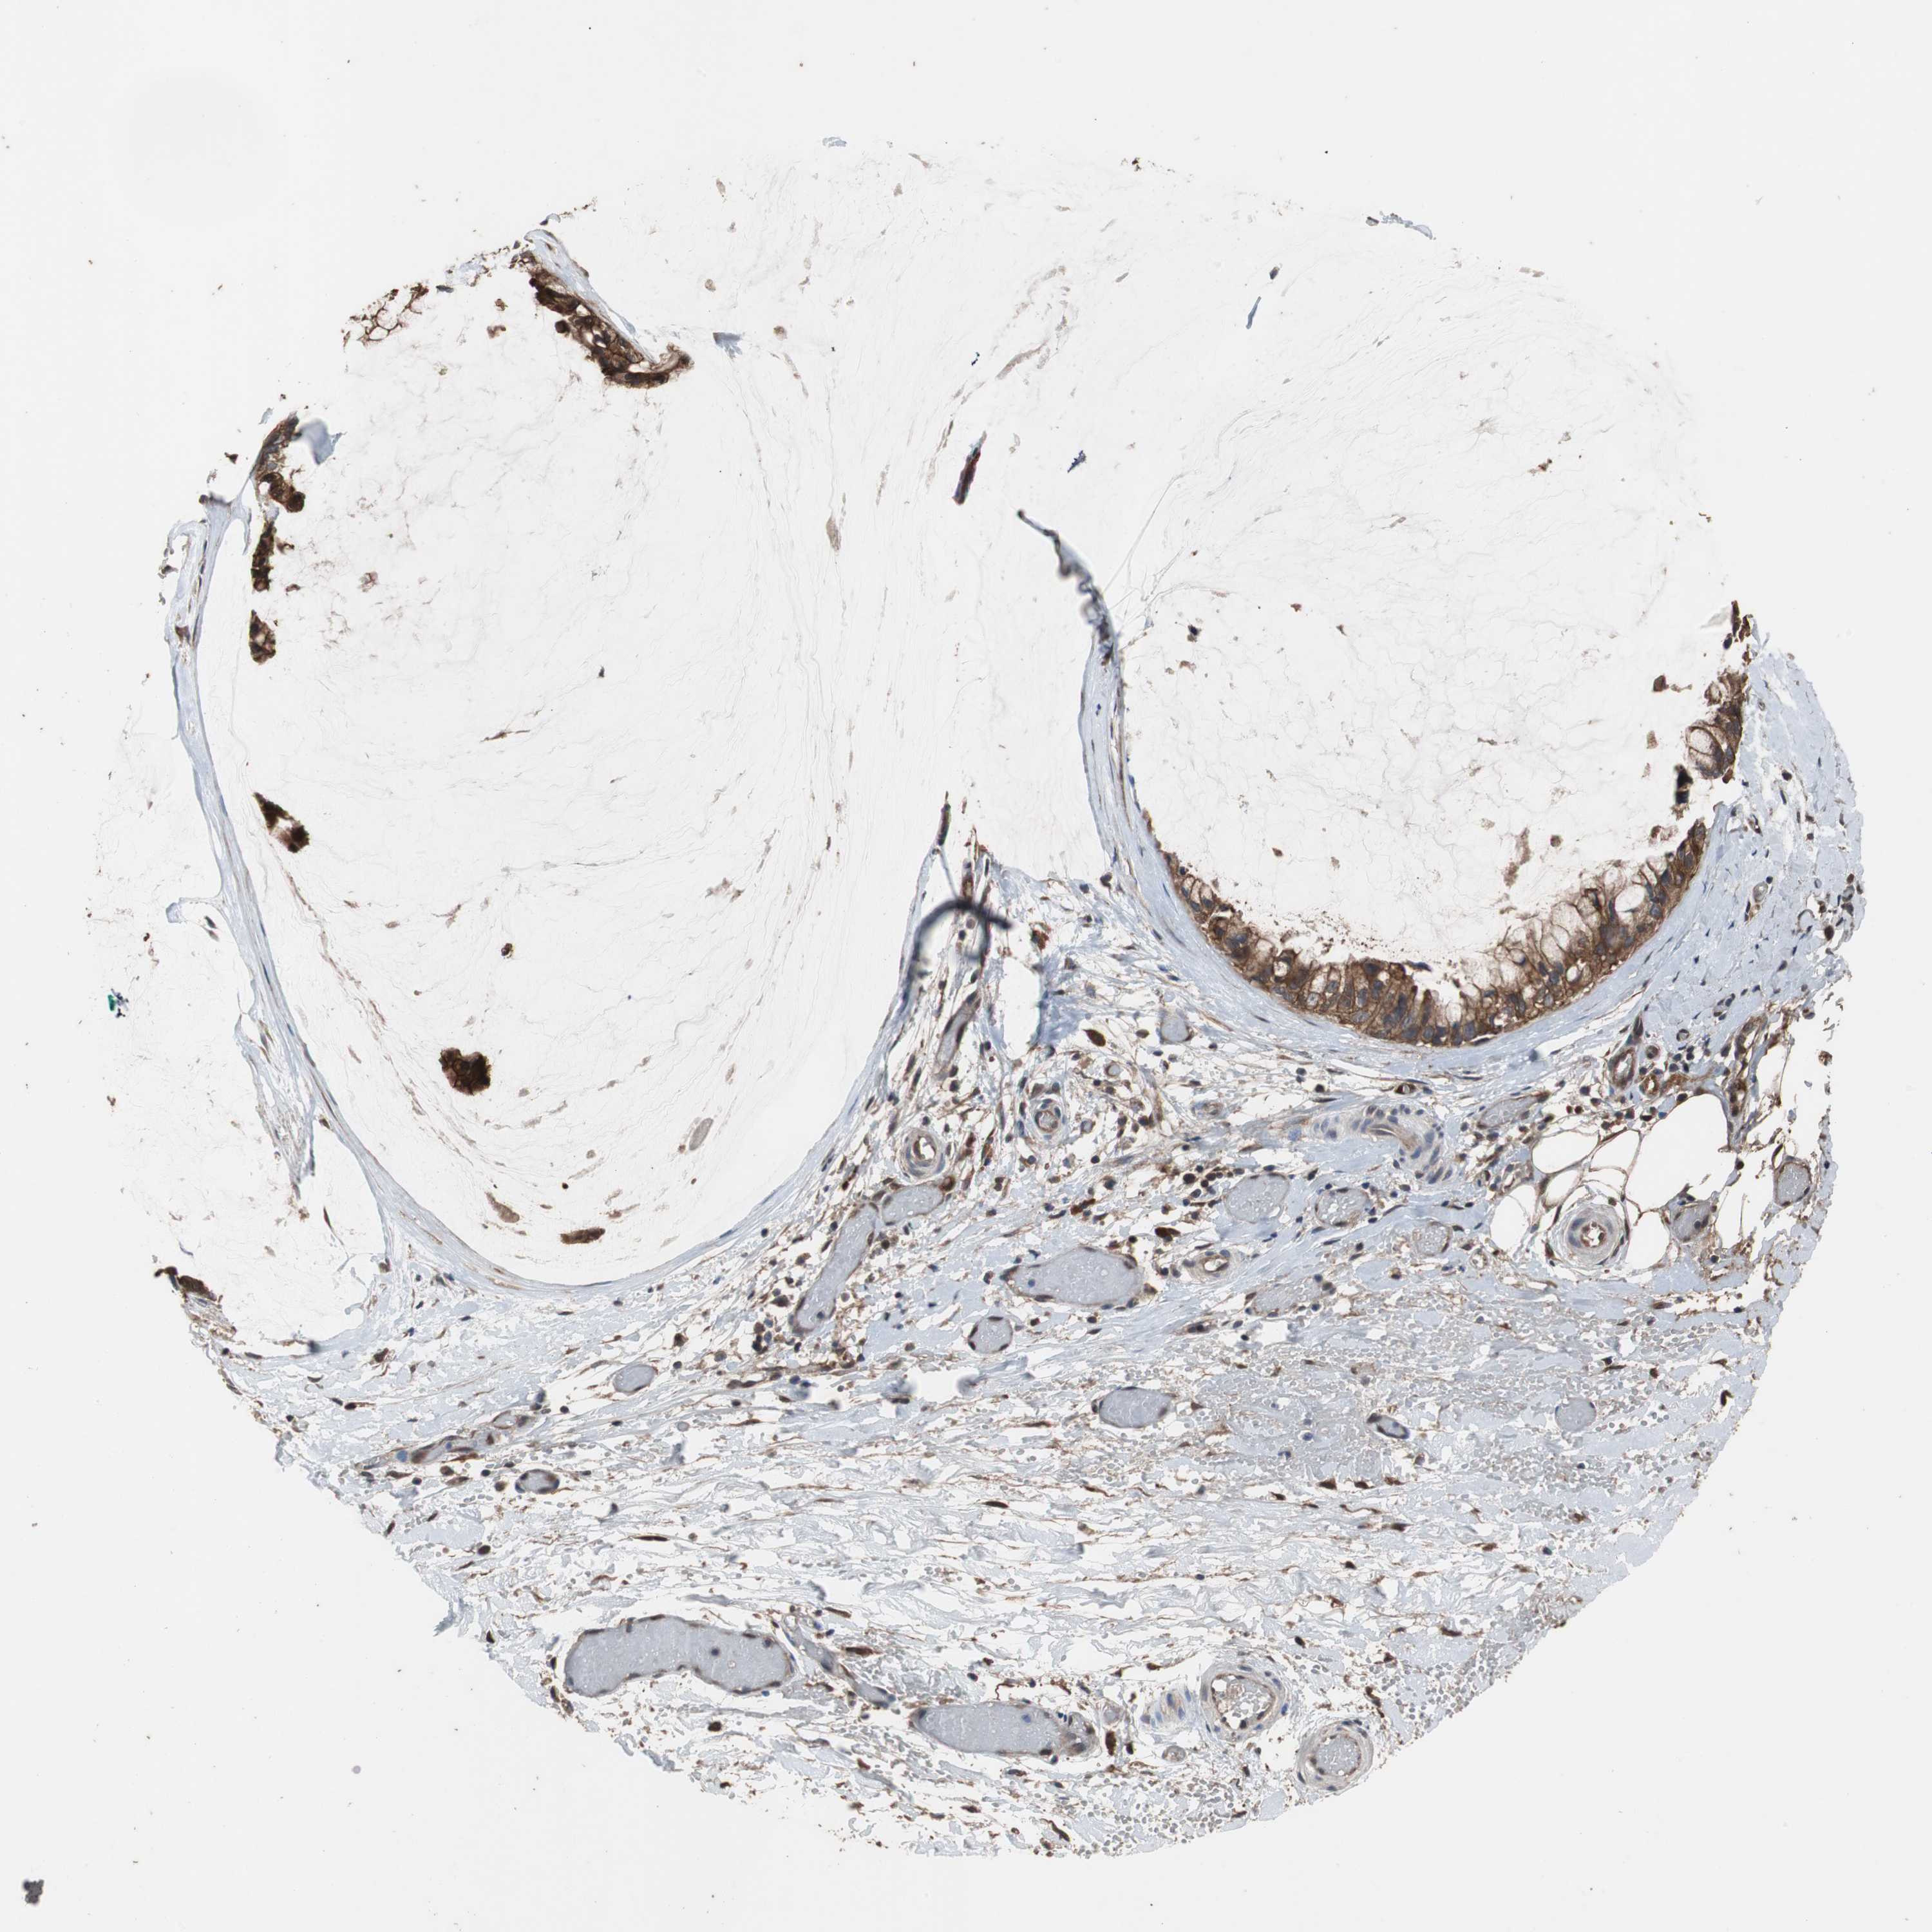

OVARIAN CANCER - Protein expressioni

A mouse-over function shows sample information and annotation data. Click on an image to view it in a full screen mode. Samples can be filtered based on level of antibody staining by selecting one or several of the following categories: high, medium, low and not detected. The assay and annotation is described here.

Note that samples used for immunohistochemistry by the Human Protein Atlas do not correspond to samples in the TCGA dataset.

Antibody stainingi

Antibody staining in the annotated cell types in the current human tissue is reported as not detected, low, medium, or high, based on conventional immunohistochemistry profiling in selected tissues. This score is based on the combination of the staining intensity and fraction of stained cells.

Each image is clickable and will lead to virtual microscopy that enables deeper exploration of all samples and also displays staining intensity scores, fraction scores and subcellular localization as well as patient and tissue information for each sample.

Antibody HPA006881

Cystadenocarcinoma, serous, NOS

Cystadenocarcinoma, mucinous, NOS

Carcinoma, endometroid